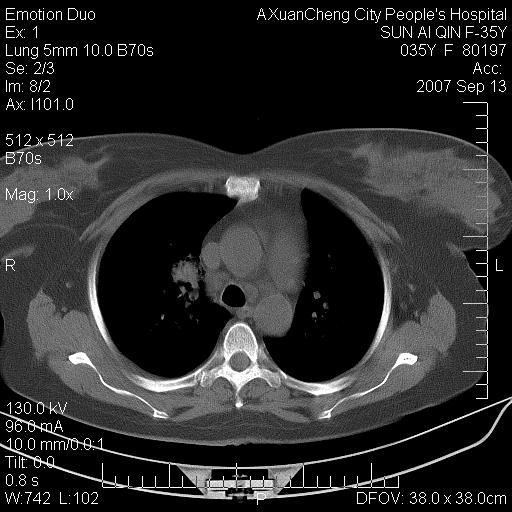

以下是引用天南地北在2007-9-13 13:43:00的发言:[br]考虑双肺、肺门侵润

以下是引用ydx_74在2007-9-13 15:42:00的发言:[br]仅看片,考虑右上肺癌并双肺转移,结合病史,考虑肺门、肺内淋巴侵润

以下是引用同在2007-9-13 15:08:00的发言:[br]支持肺门及双肺侵润.